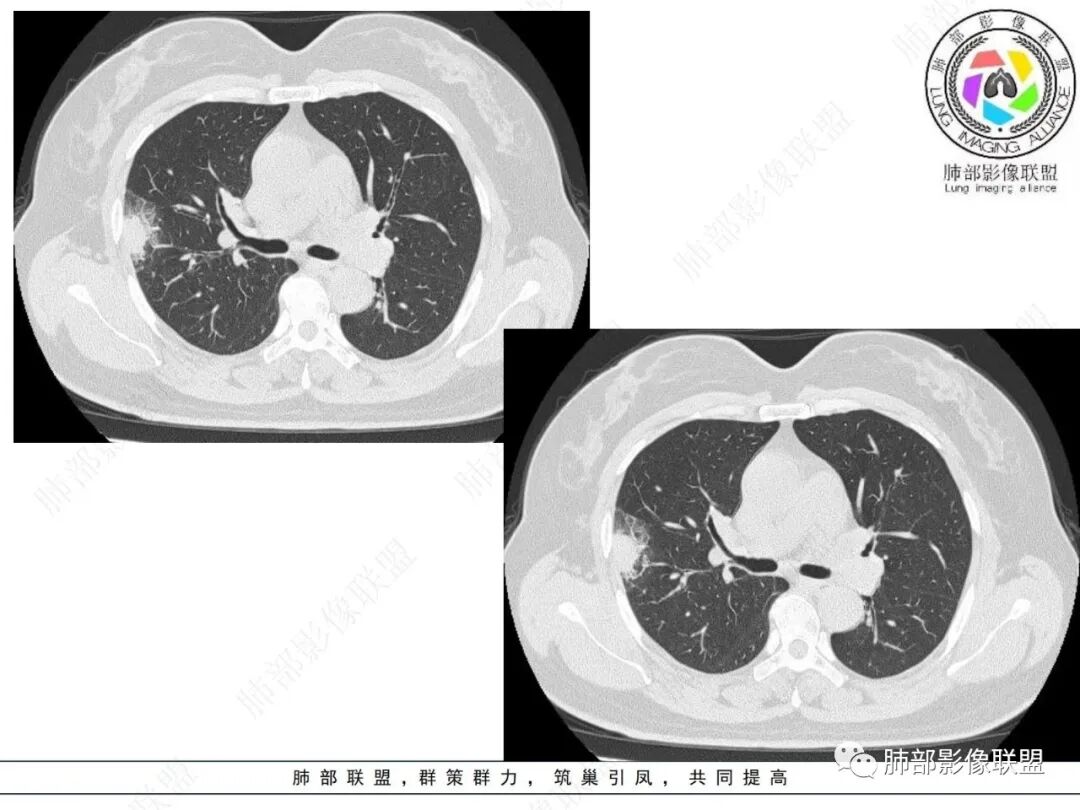

2.影像特点:

右肺上叶胸膜下混合磨玻璃团片影。

周围磨玻璃部分间杂条索状高密度区,密度欠均匀(可疑重力分布趋势),其磨玻璃影边界大多较清楚或可分辨,部分“L型”边缘,提示小叶间隔阻挡可能。血管穿行自如,可疑远端支气管进入。

实性部分较密实,不规则,隐约见棘突或刺状突起,未见钙化、空洞或液化区,实性边缘可见斑状略低密度间隙(借用王兆宇老师课件,称其呈“松软”的形态)。动脉期实性部分较明显不均匀强化,如果有完整增强图,还可以观察内部血管情况。

纵隔窗相对肺窗病灶相对小,仅部分实性影呈现。病灶张力不高,相邻胸膜增厚(糊墙),未见明显胸膜牵拉凹陷。

未见卫星病灶,远处未见磨玻璃结节影。

双肺门及纵隔未见明显增大淋巴结。心包及胸腔未见积液。